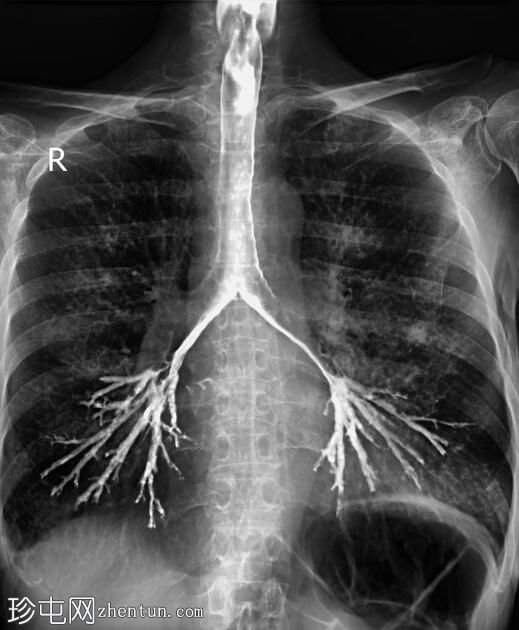

正位

正位和侧位图像显示造影剂在咽部积聚,并伴有钡剂误吸至气道和支气管树。未见

肺

实变。

此外,胸椎存在退行性改变,表现为终板硬化和边缘骨赘形成。

透视图像显示钡剂误吸覆盖喉部和气管支气管树。